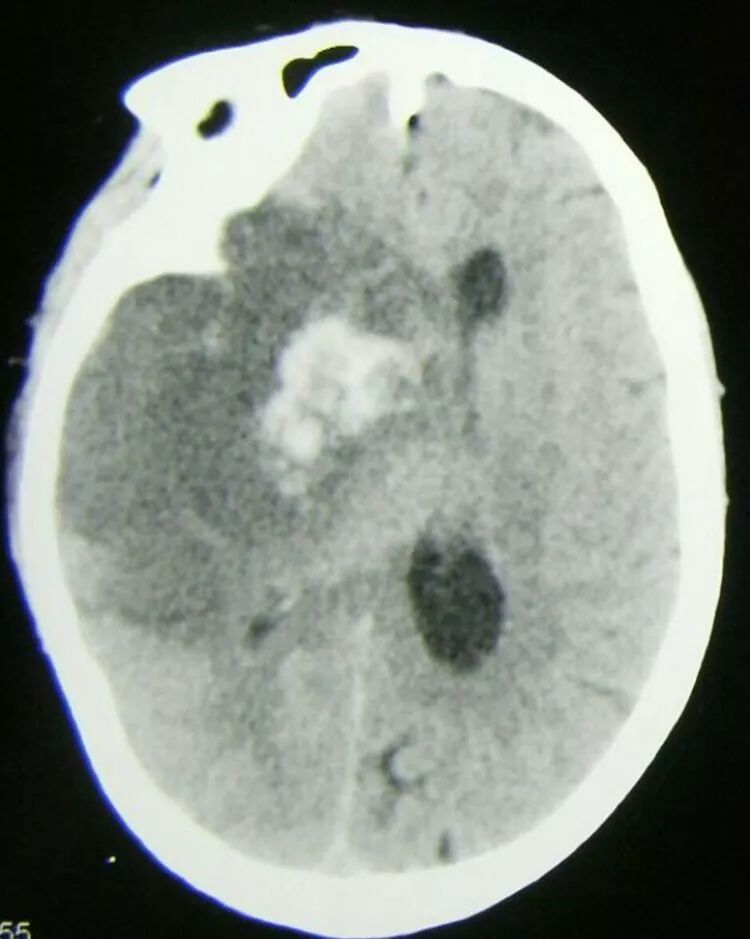

cT显示:右侧半球大面积低密度灶,内部存在高密度出血性,中线明显移位,鞍上池及三脑室消失。

术后患者瞳孔恢复至等大,意识好转,刺激睁眼,cT复查:血肿清除满意,中线复位,三脑室及脑池显示清楚。